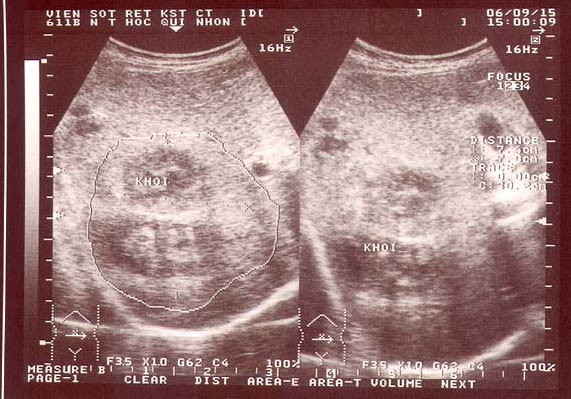

Trong giai đoạn mạn tính:

Trong giai đoạn này, hình ảnh trên SA điển hình thường là đa ổ nhỏ, li ti có thể vừa gặp trong nhu mô gan vừa gặp trong đường mật (3,13%), bao gồm OMC; nhưng phần lớn là hình ảnh thả nổi (floating) hoặc vết (trace) tăng âm di động bên trong túi mật hoặc OMC mà không kèm bóng cản với tỷ lệ 1,84%, có thể là sán di chuyển hoặc xác sán chết dính lại. Một dấu hiệu nữa không đặc trưng cho giai đoạn mạn tính là hình ảnh dãn, phù nề và dày thành túi mật (2,52%), đường mật (2,85%) không đều các đoạn, các dầu hiệu này cũng thường gặp trong bệnh cảnh viêm xơ đường mật hoặc viêm đường mật lan tỏa trên cơ địa suy giảm miễn dịch HIV/AIDS (Mansoeu Ghanael và cs., 2006). Kết quả ở đây tương tự như nhận định của nhiều tác giả báo cáo trên thế giới, đặc biệt các nghiên cứu tại Cuba cũng cho một số hình ảnh tương tự: những vệt thẳng tăng âm trong túi mật, dãn đường mật và nhất là dãn OMC đi kèm với vệt tăng âm bên trong lòng OMC hoặc túi mật (Orhan S và cs., 2004; Gulssen và cs., 2006; A. Fica và cs., 2012).

Nói chung, giai đoạn cấp tính thì tổn thương tập trung ở nhu mô, đặc biệt ở các Hạ Phân thùy gan bên (P) và quanh tĩnh mạch cửa. Các đặc điểm liên quan đến hệ đường mật thay đổi khác nhau tùy vị trí và có hình ảnh đặc trưng thuộc giai đoạn mạn. Một số ca thấy có dãn đường mật, song tìm dấu vết của sán lại không có. Khả năng dãn ở đây là hậu quả của sán đã đi qua đường mật, đến khi được phát hiện thấy dãn chỉ là di chứng của vài ngày trước đó.

Nghiên cứu khảo sát đã phát hiện các vùng tăng âm nhỏ không có bóng lưng kèm với dãn đường mật có thể sán đang ở trong, điểm này có thể phân biệt được với sỏi hoặc vật thể khác của đường mật (có bóng lưng). Lẽ đương nhiên, một số ca sán dính chặt vào thành túi mật, khi đó việc phân biệt sán hay polyp dạng tuyến (adenomatous polyps) thì rất khó vì đều có tính chất tăng âm và không bóng lưng. Nếu một vài con sán di động thì quá dễ dàng để phân biệt các tình huống trên.